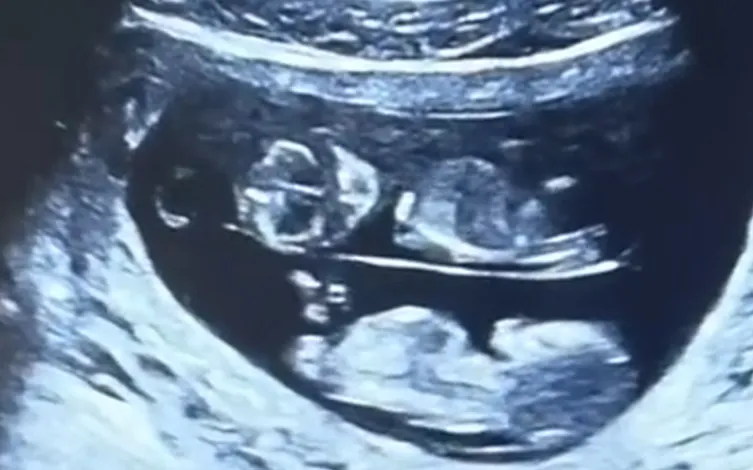

天塌了!上海老夫妻的准儿媳,两次怀上“双胞胎”,前后花了80多万,却都生不下来!